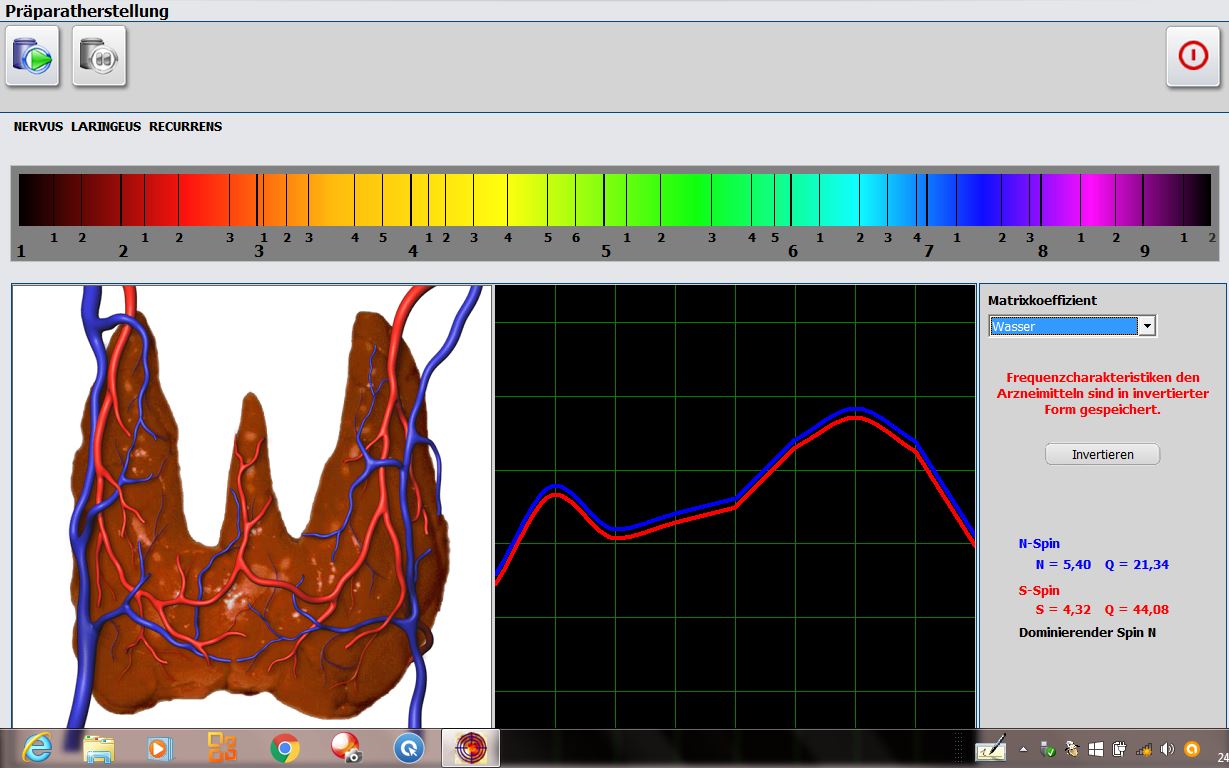

Präparateherstellung in der nichtlinearen Systemdiagnostik und -therapie

Analyse eines Therapievergleichs in der nichtlinearen Systemdiagnostik und -therapie

Einsatz verschiedener NLS-Systeme zur Fehlerminimierung und Vergleich mit herkömmlichen diagnostischen Verfahren wie der Magnetresonanz-tomografie (MRT) und Röntgen